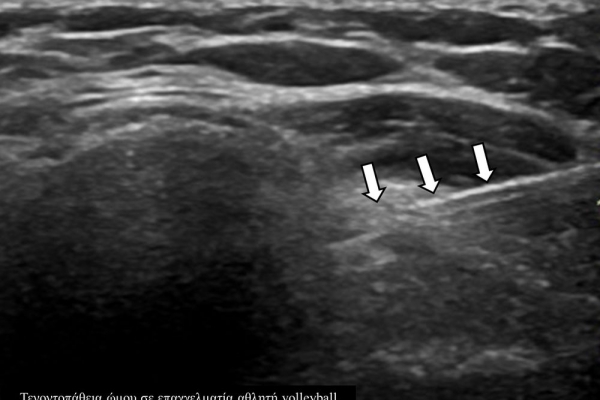

- Οξείες και χρόνιες Τενοντίτιδες και Τενοντοπάθειες (τενοντίτιδα αχιλλείου, επιγονατιδικού,οπισθίων μηριαίων, υπερακανθίου του ώμου)

Η έγχυση γίνεται πάντοτε με την βοήθεια υπερηχογραφικού ελέγχου ώστε να είμαστε απόλυτα σίγουροι για το σημείο έγχυσης τοπικά.